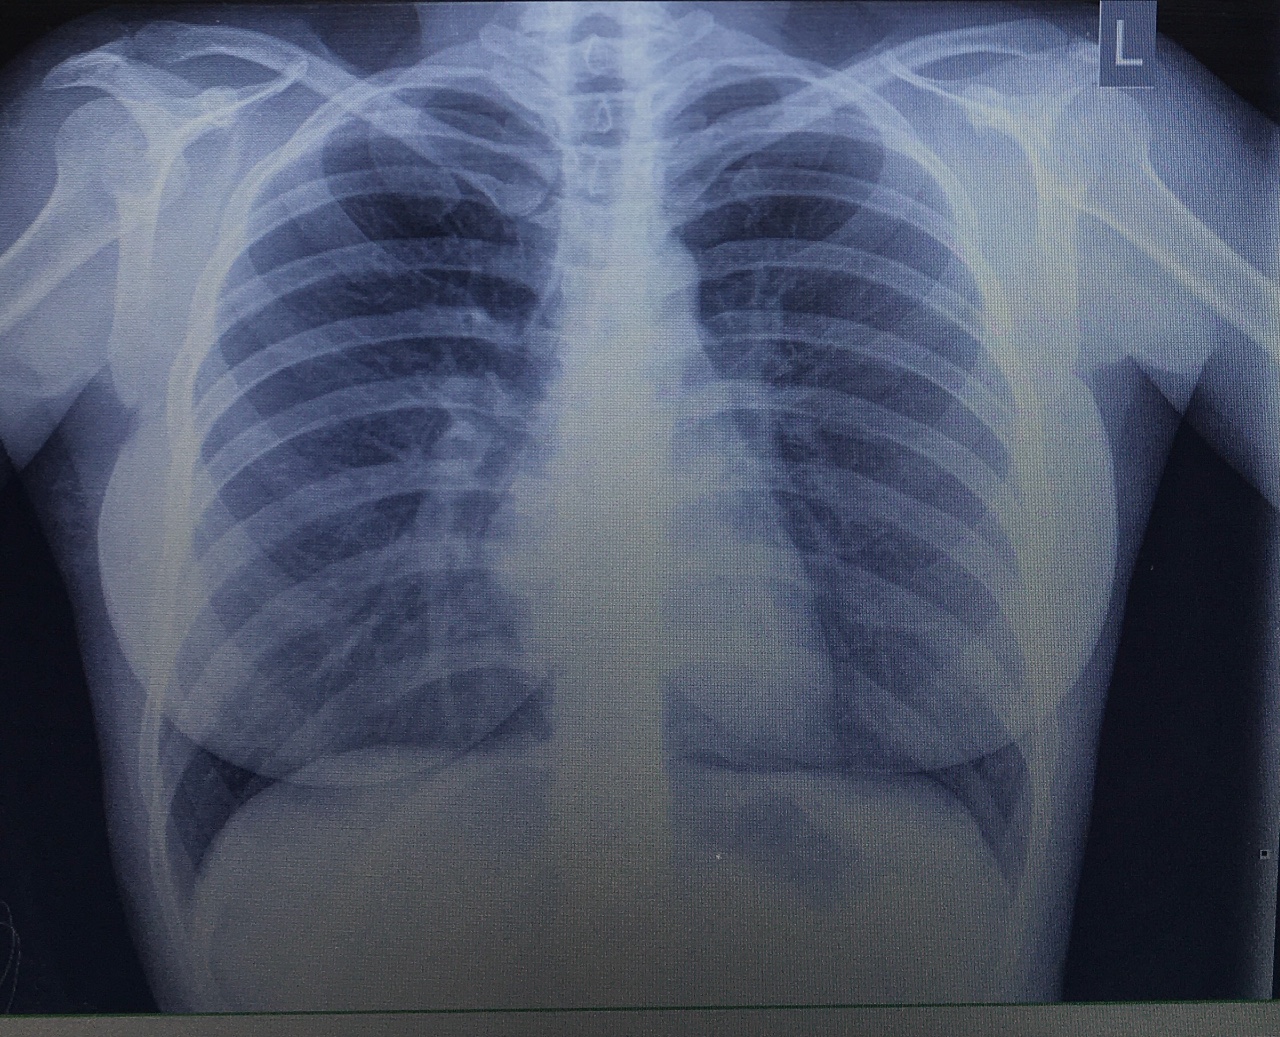

Снимок грудной клетки здорового ребенка: примеры и диагностика

Раздел: Мудрость в объективе